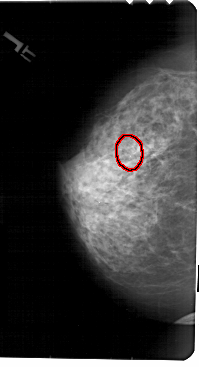

A_1531_1.LEFT_CC

LEFT_CC LINES 5491 PIXELS_PER_LINE 2971 BITS_PER_PIXEL 12 RESOLUTION 43.5 OVERLAY

FILE: A_1531_1.LEFT_CC.OVERLAY

TOTAL_ABNORMALITIES 1

ABNORMALITY 1

LESION_TYPE CALCIFICATION TYPE PLEOMORPHIC DISTRIBUTION CLUSTERED

ASSESSMENT 4

SUBTLETY 4

PATHOLOGY MALIGNANT

TOTAL_OUTLINES 1